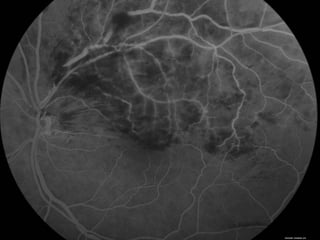

Angiografia 10/02/2009

Caso Clínico

• ANGIOGRAFICO

– Define edema macular, a perfusão da rede capilar para-foveal e a presença de

neovasos.

– Mostra o retardo artério-venoso na arcada comprometida e a presença de

áreas isquêmicas e de vazamento tardio.

Caso Clínico Exame Oftalmológico: AcuidadeVisual c/c: • OD = 20/20 • OE = 20/100 (metamorfopsias) • Add: +3,00 Biomicroscopia: Normal FO: OD: Normal. OE: Hemorragias retinianas temporal superior. Edema Macular Solicitado: Angiografia e OCT